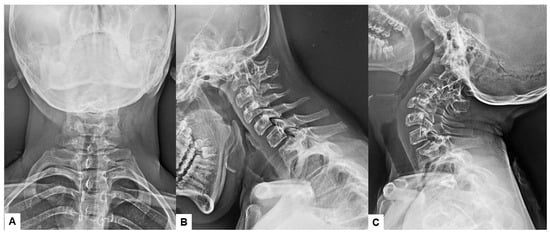

2.6. One Year Follow-Up